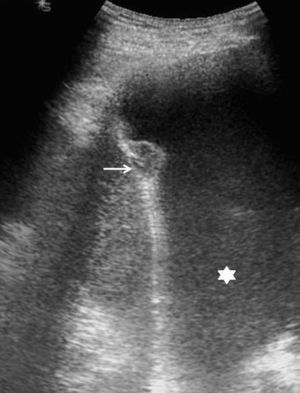

El aspecto ecográfico de un derrame pleural depende de su naturaleza, causa y cronicidad. Por sus características ecográficas los derrames pueden dividirse según presenten ecos internos, septos (gruesos o finos y móviles) y/o nodularidad pleural, o sean totalmente anecogénicos. Se ha demostrado que la ecografía es más sensible que la TC para demostrar la existencia de septos (fig. 1) en el interior de un derrame pleural4,18. La presencia de ecos, septos o nódulos permite catalogarlo de exudado19. La ausencia de estos hallazgos, es decir, el hecho de que se trate de un líquido anecogénico, no permite determinar que sea un trasudado, dado que los exudados se pueden presentar de esta manera19.

En pacientes de difícil movilización, como los ingresados en unidades de cuidados intensivos, la ecografía también es útil para determinar si las alteraciones visibles en la radiografía anteroposterior en decúbito supino corresponden a derrame pleural o a consolidaciones parenquimatosas (fig. 2). Además, como se comenta más adelante, también permite la obtención de líquido pleural de forma rápida y segura.